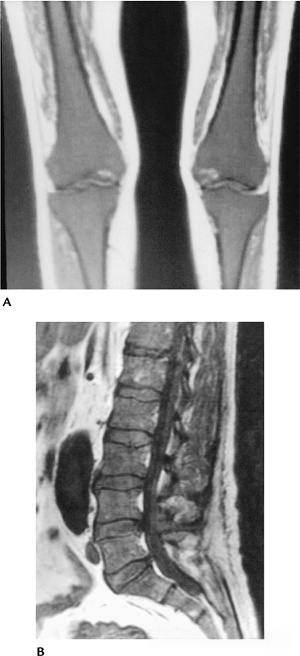

图-1骨髓模式。骨盆、膝关节、肩关节和脊柱T1WI像。在成人中,骨盆的骨髓主要为脂肪性骨髓,除了髋臼区(箭头)有小面积的红骨髓。年长成人膝关节也有高信号的脂肪性骨髓。20岁患者肩关节骨骺高信号脂肪性骨髓,肱骨骨干和肩胛盂中有红骨髓。脊柱显示主要为黄骨髓,但由于多发转移,存在低信号区。